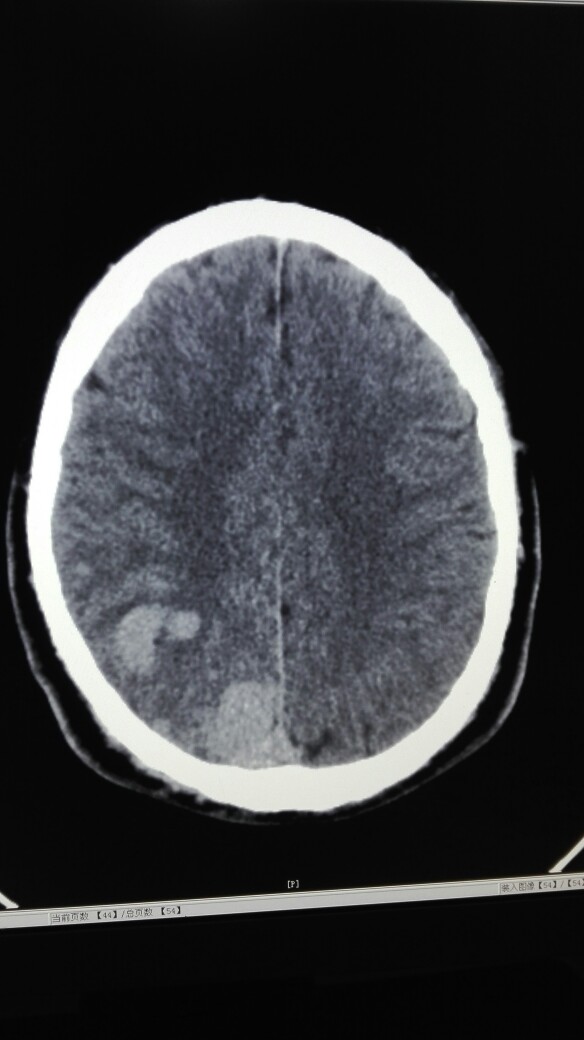

患者男,34岁,偶尔头部疼痛就诊。行头部CT扫描示:右枕叶区团片样密度增高影,其内见扭曲条状影及点状钙化灶,当班医生考虑右枕叶脑肿瘤可能性大。我觉得不像是脑肿瘤,理由是:1.病灶占位效应不明显;2.未见水肿带;3.邻近颅骨未见改变。个人意见考虑是血管畸形(静脉血管瘤?),建议增强检查或DSA。因病灶紧贴大脑镰,所以还需与脑膜瘤鉴别。